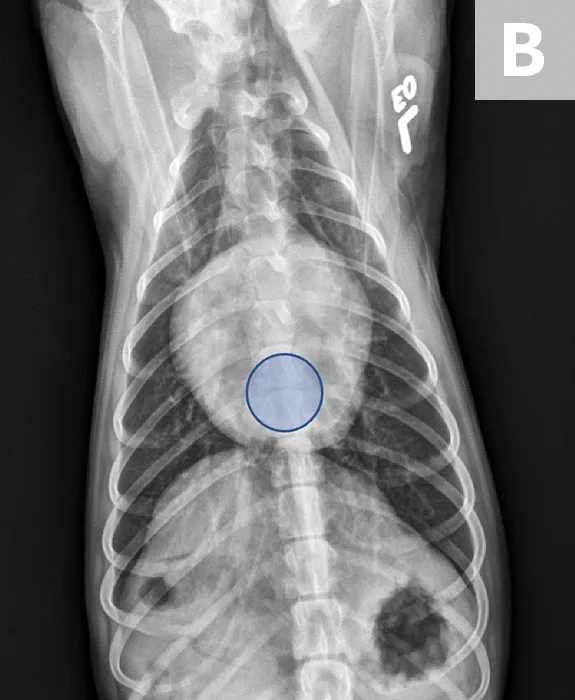

FIGURE 2

VLAS measurement in a dog with suspected stage B2 MMVD using a right lateral radiograph (A). A caliper was used to measure from the center of the most ventral aspect of the carina to the most caudal aspect of the left atrium, where it intersects with the dorsal border of the caudal vena cava. This measurement was transferred to the cranial aspect of T4 and extended caudally along the thoracic vertebrae. The number of vertebrae this line transversed was rounded to the nearest tenth to determine VLAS (2.8 VBUs). Stage B2 MMVD was confirmed via echocardiography. Other structures are unremarkable. An orthogonal radiograph of the patient provides a more complete evaluation of cardiac silhouette (B); normal location of the left atrium is indicated (circle).